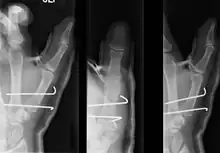

| Bennett fracture on x-ray | |

- For Bennett fractures where there is between 1 mm and 3 mm of displacement at the trapeziometacarpal joint, closed reduction and percutaneous pin fixation (CRPP) with Kirschner wires is often sufficient to ensure a satisfactory functional outcome. The wires are not employed to connect the two fracture fragments together, but rather to secure the first or second metacarpal to the trapezium.